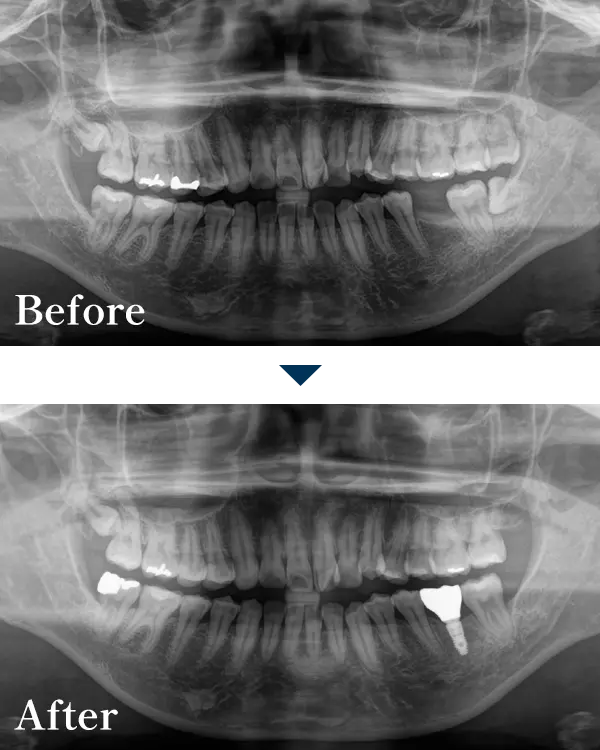

| 主訴 | 奥歯がないので、歯を入れたい |

|---|---|

| 治療内容 | 左下6番にインプラントを埋入し、 ジルコニア上部構造で治療 |

| 治療期間 | 550,000円(税込) |

| 標準費用【自費】 | 約4ヶ月 |